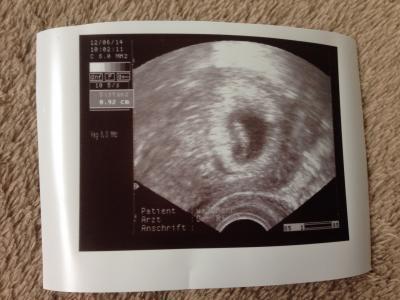

... und alles ist in Ordnung. Bin heute 6+6, Knirps misst ca 9,5 mm und das Herzchen schlägt. Der ET wurde auf den 31.1.15 datiert.

Bild zu Hatte 1. VU... - Forum für Januar - Mamis